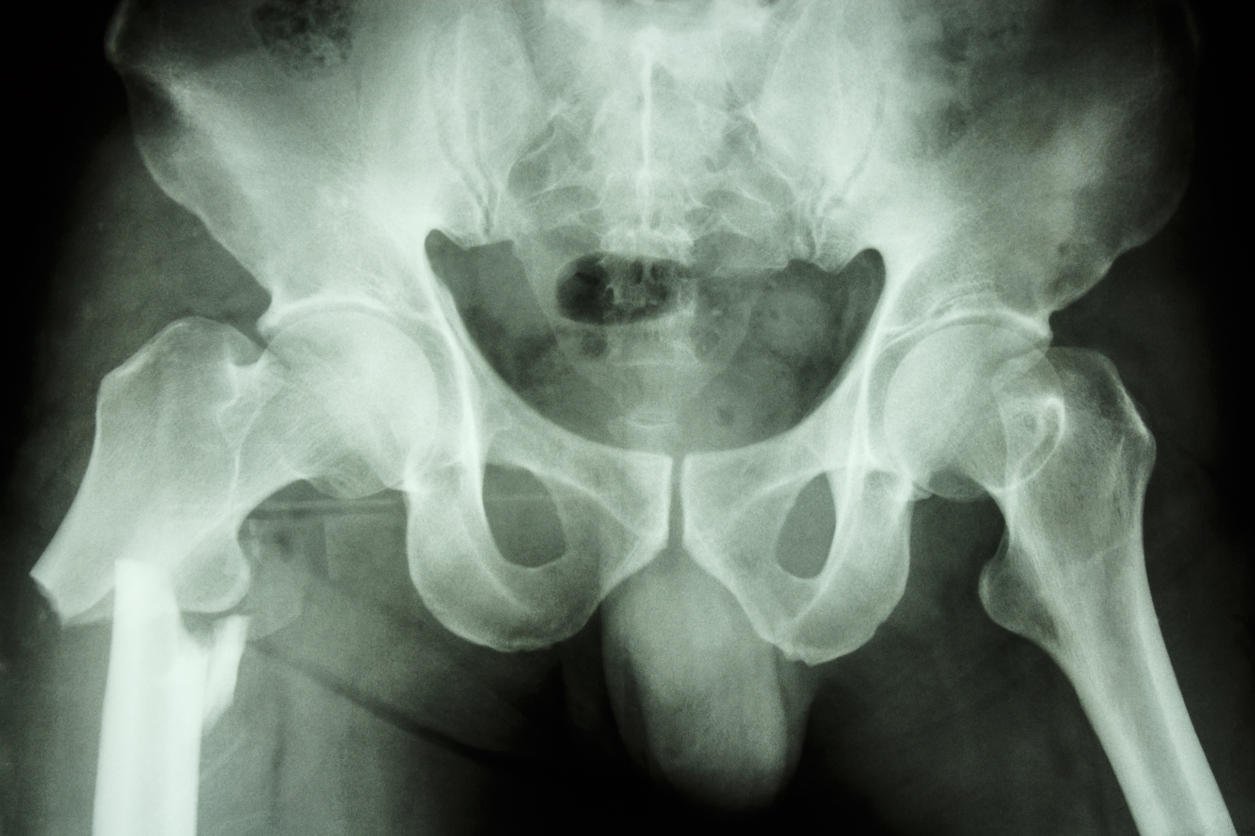

film radiographie pelvienne ap show fracture fémur droit (os de la cuisse)

La diaphyse fémorale est la partie longue de l'os du fémur qui se trouve dans la cuisse. Les principales fractures fémorales se situent vers le col du fémur, la partie la plus fragile de l'os, vers le bassin. La fracture du fémur se situe rarement sur la diaphyse. Quel traitement envisager en cas de fémur cassé ?